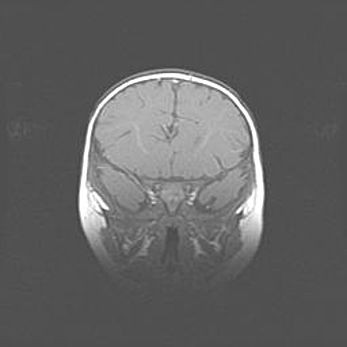

Подострая гематома правой гемисферы мозжечка.

Наружная гидроцефалия.

Возраст: 15 дней

Вес: 3100 г

Пол: женский

Окружность головы: 37 см

Срок гестации: 35-36 недель

При открытой наружной форме гидроцефалии у новорожденных расширяются и переполняются субарахноидные пространства.

Кровоизлияния в мозжечок имеют две клинико-анатомические формы: полушарные гематомы и кровоизлияния в червь.

К появлению этой патологии может привести: повреждения головного мозга, возникающие в результате асфиксии и гипоксии плода при беременности, или травмы во время родов. Редко гематома мозжечка может быть результатом первичной коагулопатии и сосудистой мальформации, диссеминированном внутрисосудистом свертывании, изоиммунной тромбоцитопении.